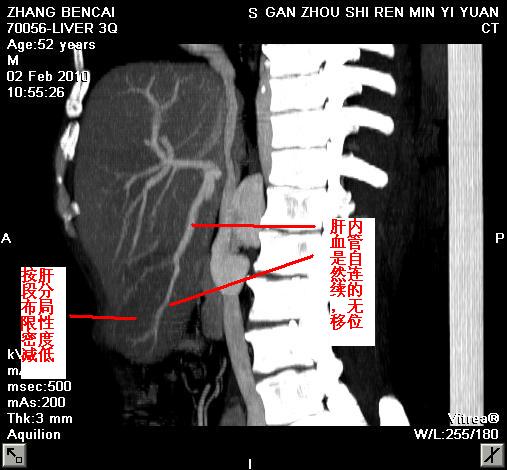

标题: CT25723结果--局限性脂肪肝 [打印本页]

该病人因胃溃疡手术,该ct是术前检查,我们考虑局灶性脂肪肝,术中探查肝脏无占位。